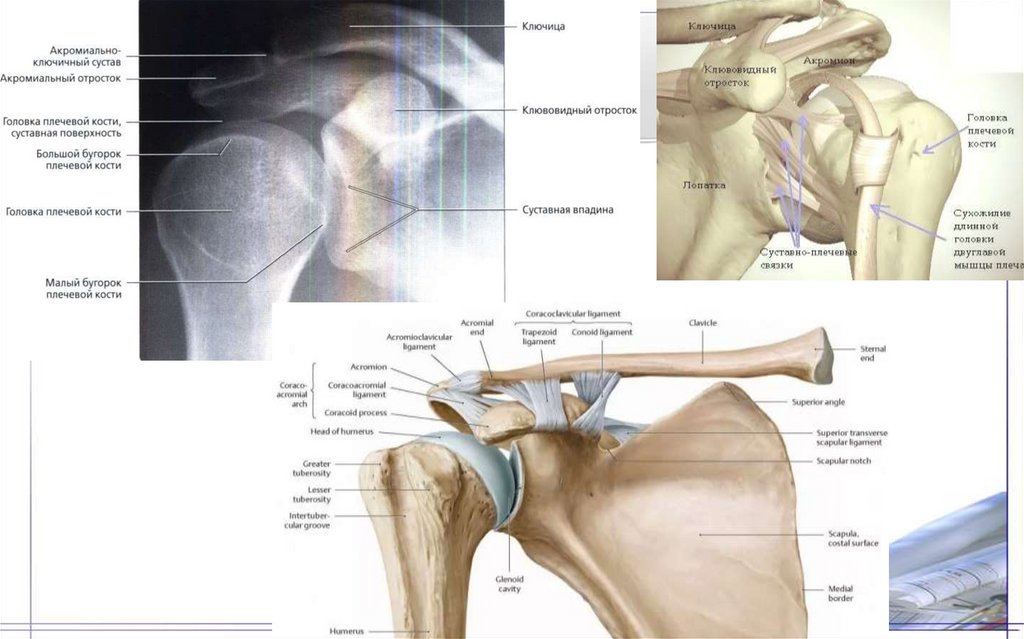

36. Плечевая кость(Humtrus)